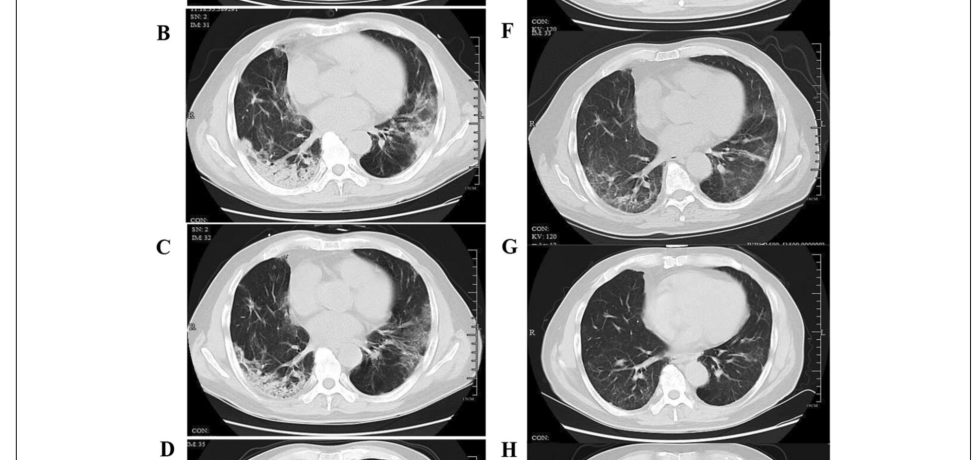

SARS-CoV-2 enfeksiyonu sonrası hastalarda Akciğer BT bulgularının bir yıllık takip sonuçları

• SARS-CoV-2 enfeksiyonu sonrası hastalarda Akciğer BT bulgularının bir yıllık takip sonuçları